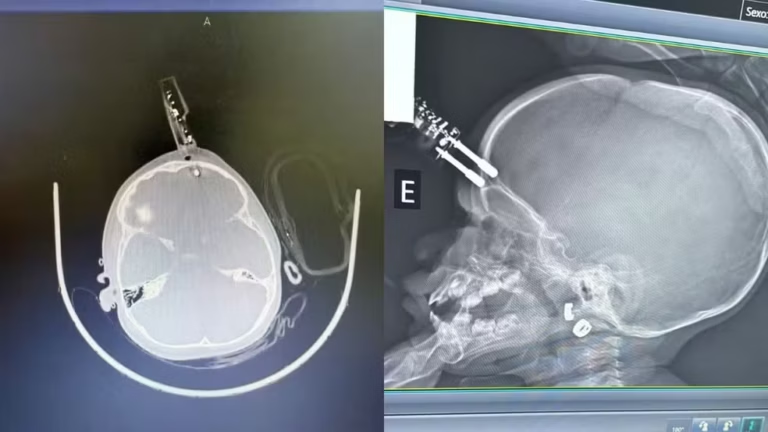

Menina fica com carregador cravado na cabeça em MG — Foto: Bruno Castro/Arquivo Pessoal

O caso aconteceu na última terça-feira (13). Segundo o neurocirurgião Bruno Castro, responsável pelo atendimento, a principal hipótese é que a criança estivesse segurando o carregador no momento da queda. O objeto perfurou o osso do crânio, próximo ao olho, e atingiu o tecido cerebral.

“A única possibilidade plausível é que ela estava com o carregador na mão e caiu junto com ele. Por azar, o objeto entrou na testa. Se tivesse atingido o olho, poderia ter causado perda da visão, o que felizmente não ocorreu”, explicou o médico.

Menina de um ano fica com carregador de celular cravado na testa após cair da cama em Divinópolis — Foto: Bruno Castro/Arquivo Pessoal

Diante da situação, a menina foi levada imediatamente ao bloco cirúrgico. O procedimento incluiu a retirada do objeto, limpeza da área, lavagem, fechamento e reconstrução da região afetada.

“A intervenção precisava ser imediata. Sem isso, o risco de hemorragia cerebral ou infecção grave seria muito alto”, destacou o neurocirurgião.